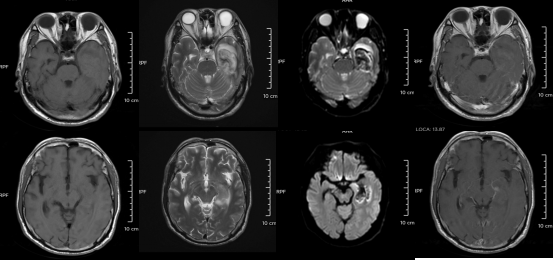

△某單純皰疹病毒性腦炎患者的醫學影像。圖源:浙江大學醫學院附屬第二醫院

但如果拖延治療,甚至會引發腦炎,可能出現癲癇、肢體偏癱、尿潴留、認知功能障礙等嚴重后遺癥,恢復時間長達3-6個月,甚至影響終身。